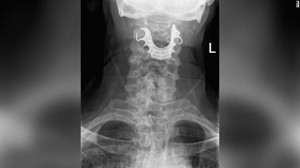

Phát sinh cơn đau vùng thượng vị, một cụ bà 60 tuổi đến bệnh viện kiểm tra thì bất ngờ phát hiện dị vật là một hàm răng giả bên trong dạ dày.